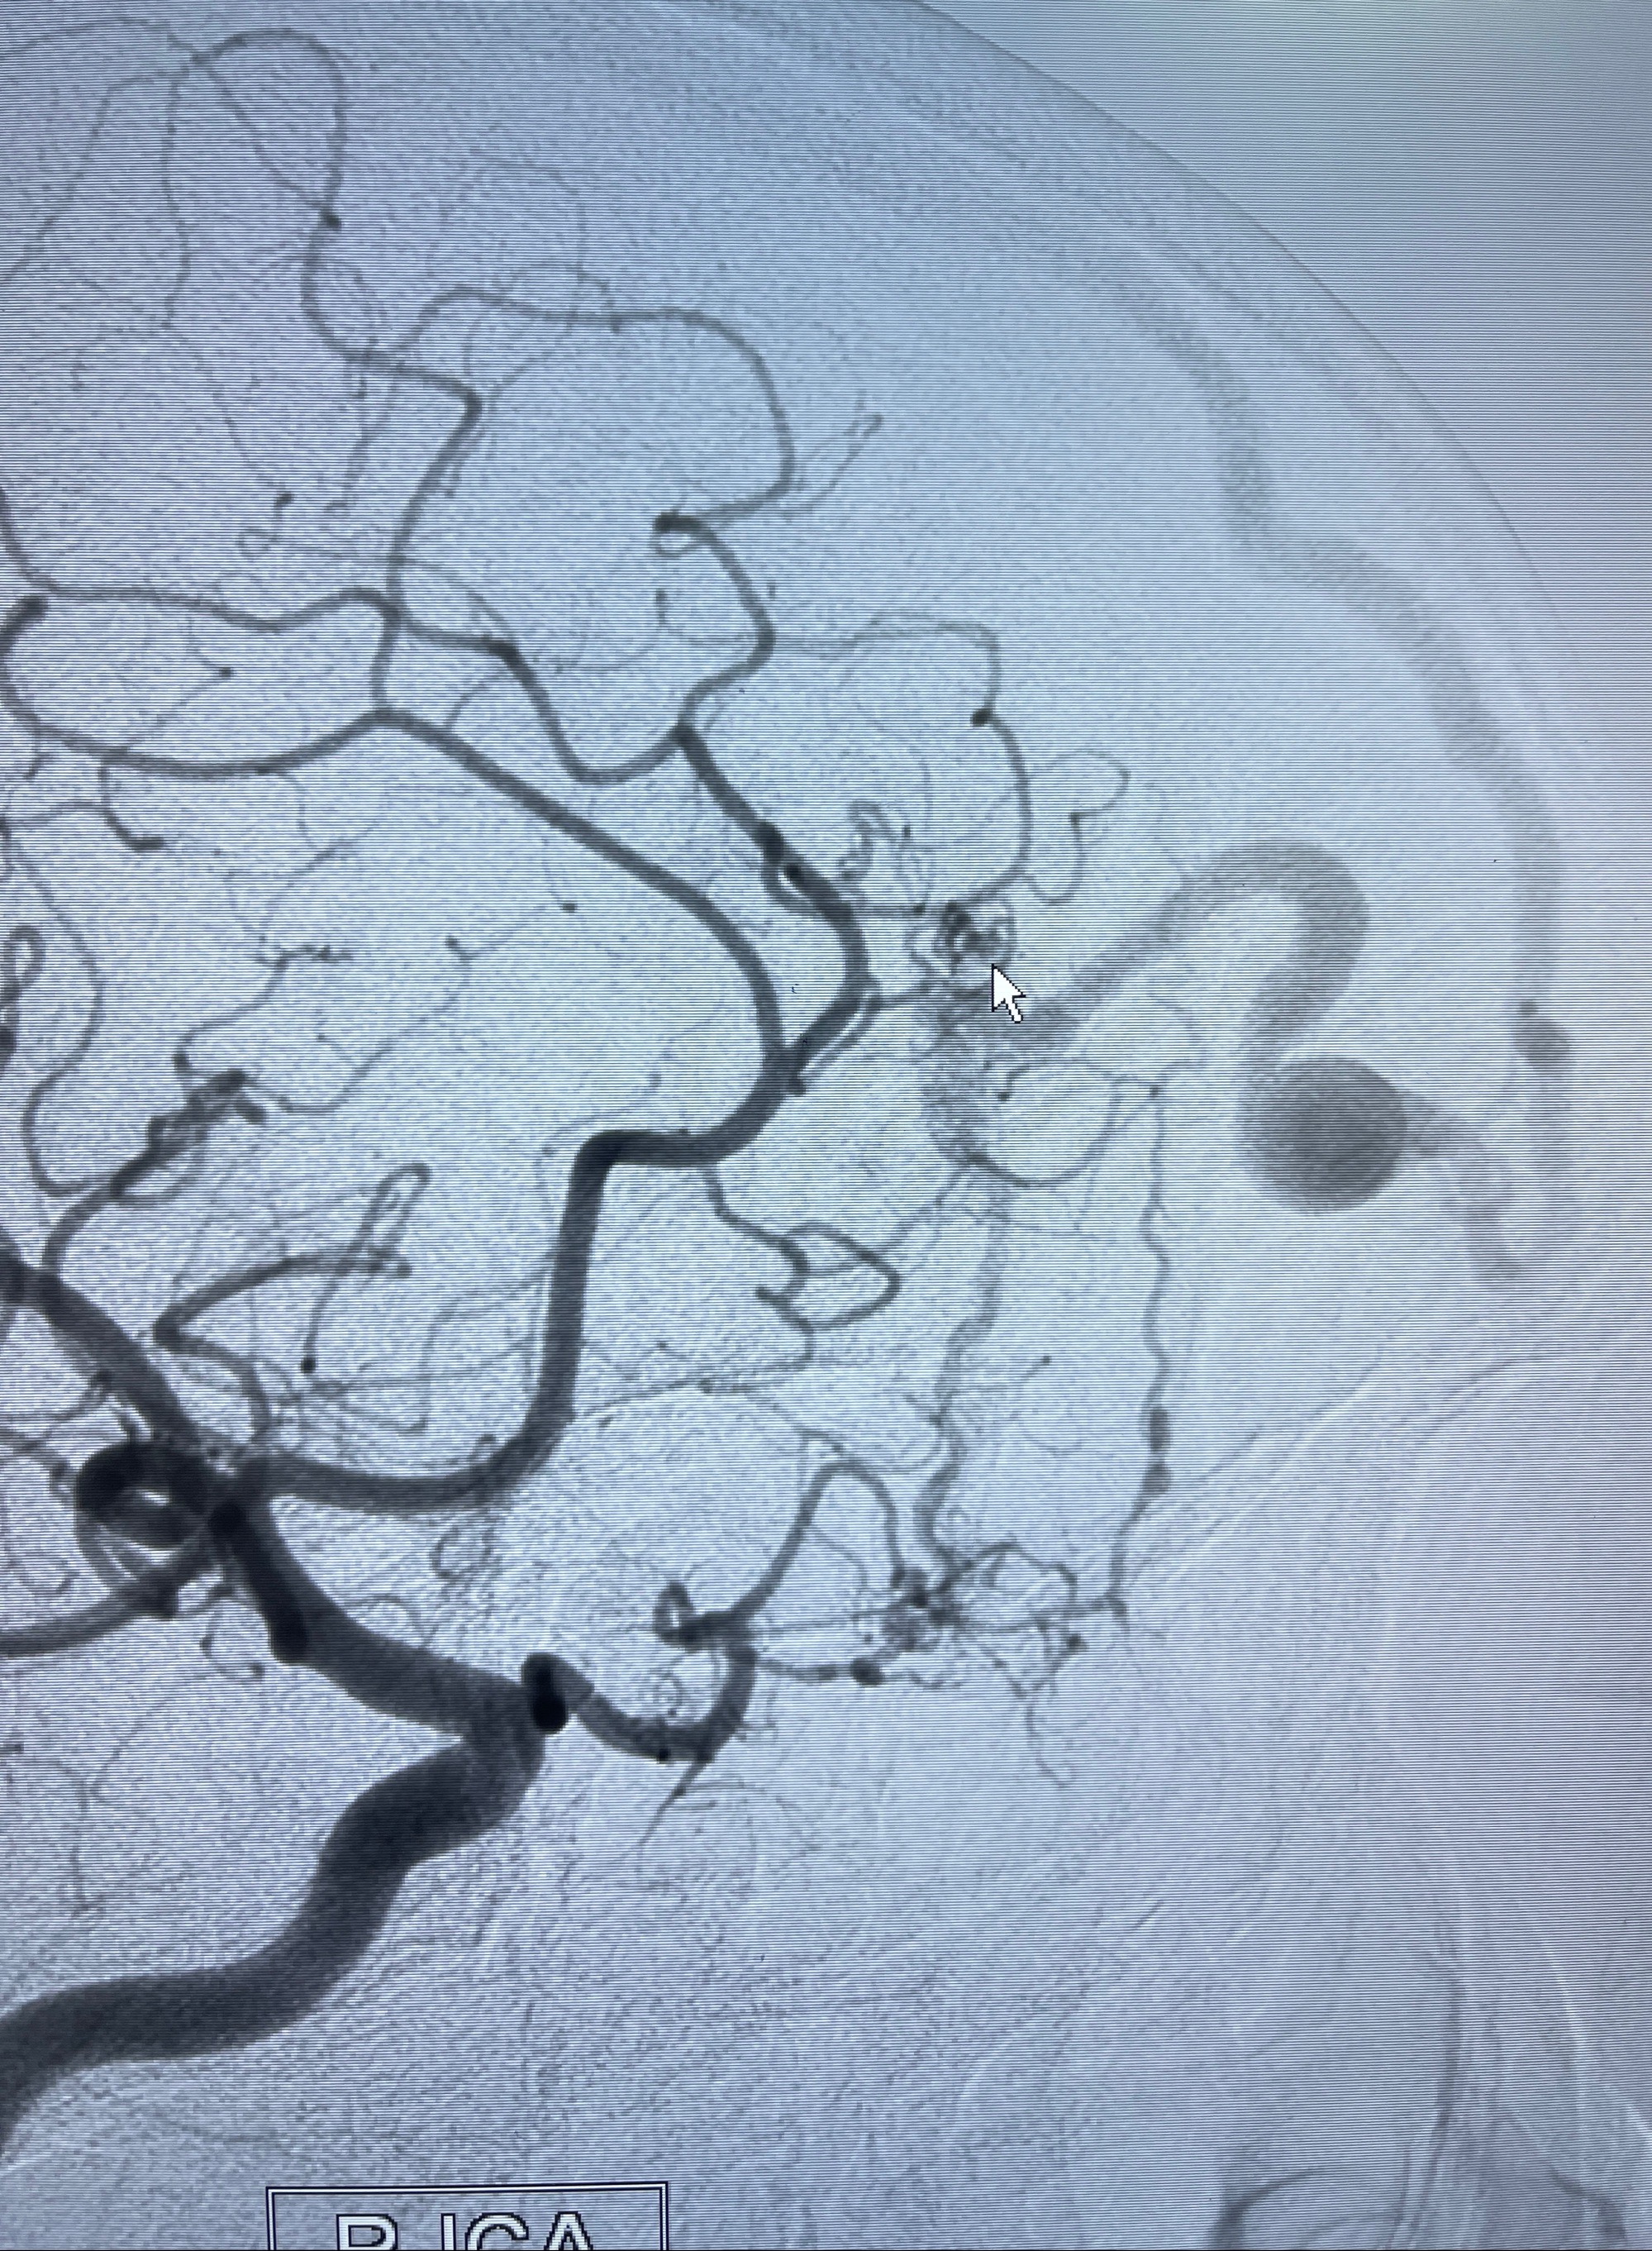

2023-09-13全脑血管造影:前颅底硬脑膜动静脉瘘,供血动脉为双侧胼周动脉、眼动脉脑膜支,静脉向上矢状窦方向引流

- 介入干预:静脉途径栓塞or动脉途径填塞?